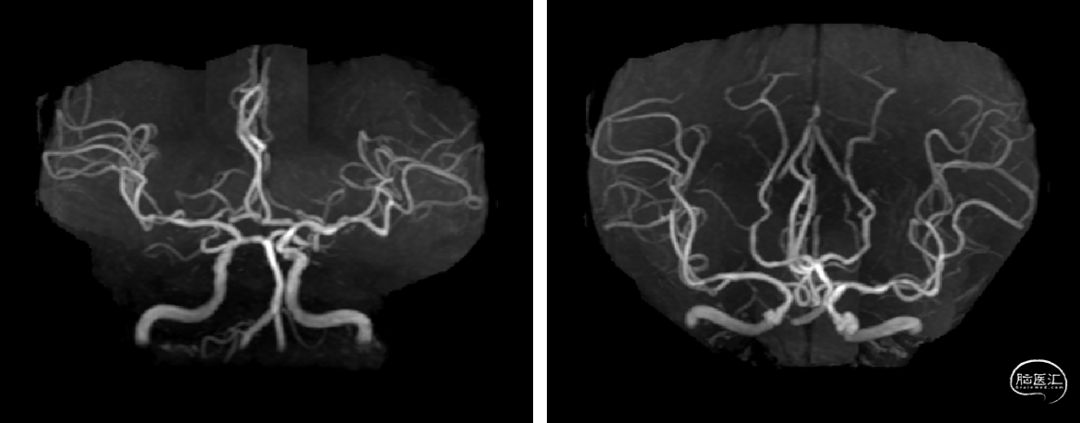

头颅核磁提示:右侧大脑半球、双侧小脑半球多发散在DWI高信号,考虑急性亚急性脑梗死;头颅MRA未发现明显重度狭窄及闭塞大血管。

急诊头颅MRA未见颅内大血管较重狭窄或闭塞。